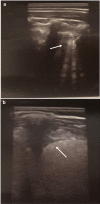

Lung ultrasound in children drowning victims in pediatric emergency department

Keywords: children; drowning; emergency; lung ultrasound.